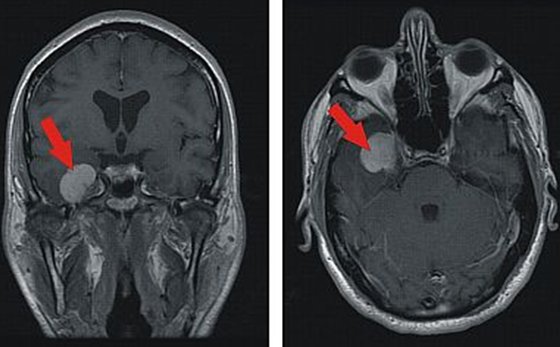

Orbitachirurgie Und Tumoren Mit Sehnervenkompression Neuroonkologisches Zentrum Clemenshospital Munster